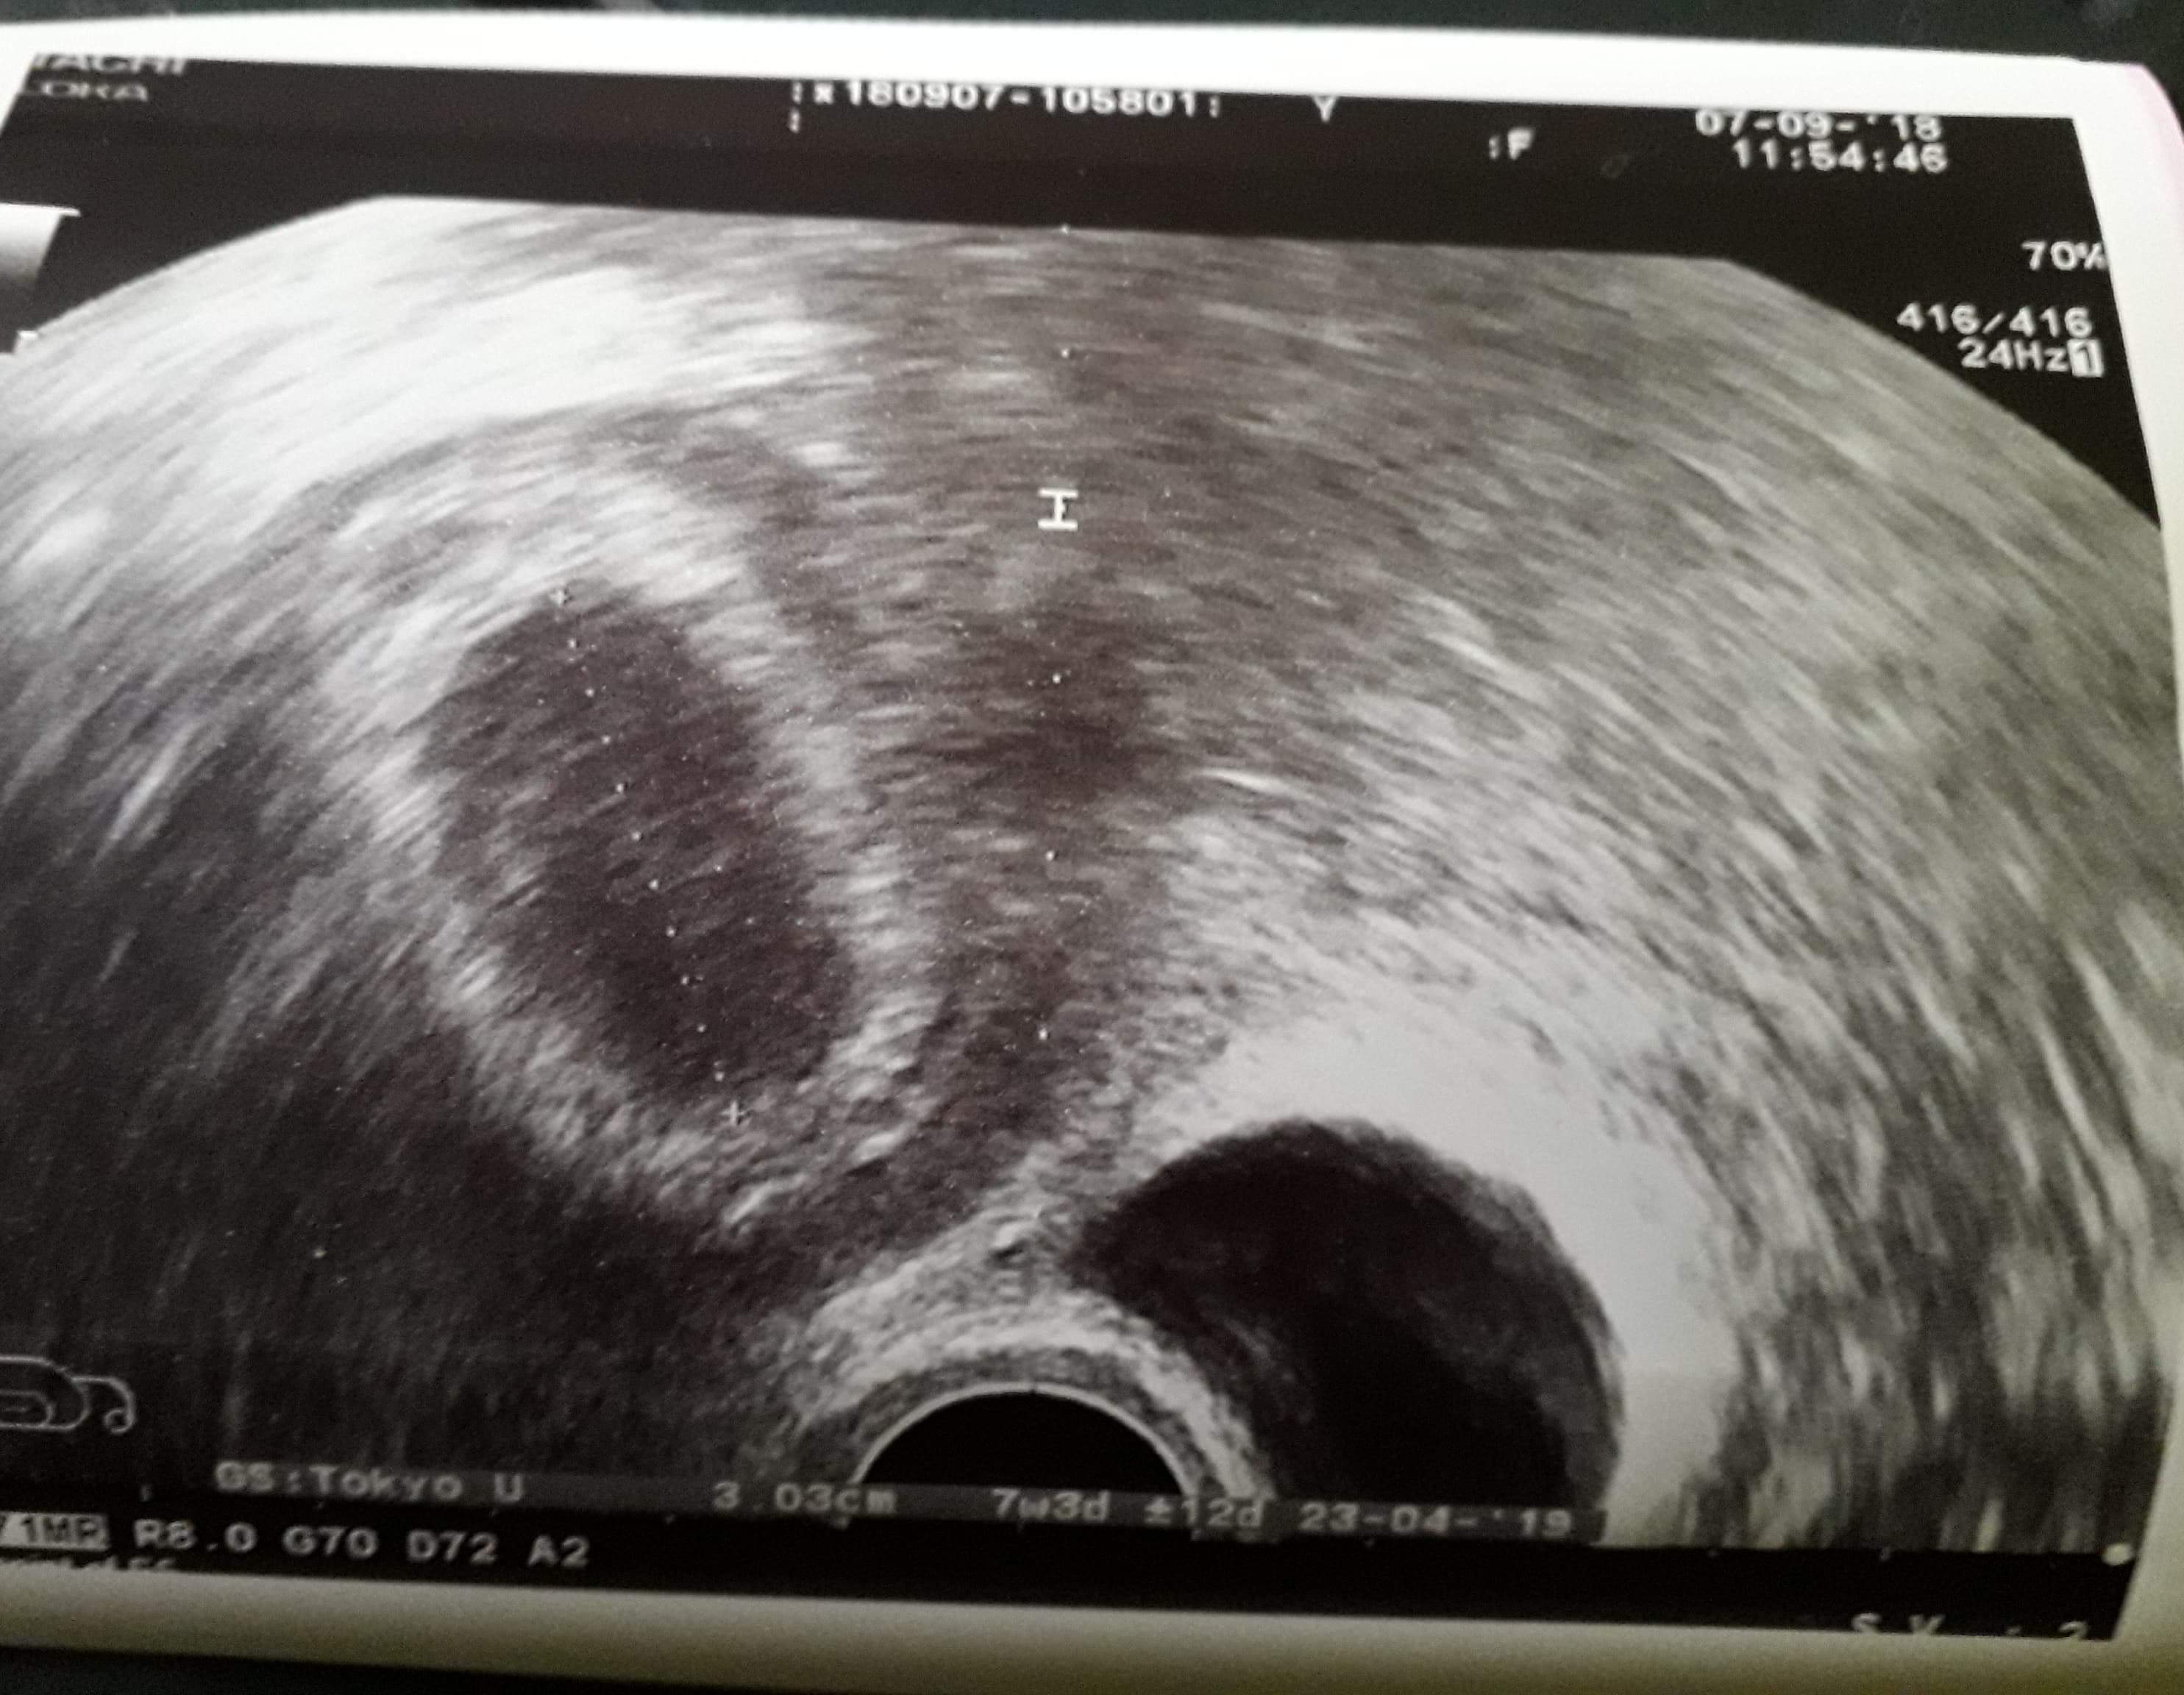

Hej. Ja miałam taki pęcherzyk 3 cm i ciałko zółte w skończonym 7 tyg a tydzień później już był zarodek z serduszkiem.

Załączniki

• received_1948361168791343.jpeg

received_1948361168791343.jpeg

388,2 KB · Wyświetleń: 1 065

Byłam. Wg moich obliczeń to 6tc+2 od miesiączki 7+2 (cykle 35 dni )

Słowa lekarza to "zarodek mały jak na ten czas " ale serce było widać jak pracuje więc nawet mam już założona kartę ciąży a maluch mierży 6,2 mm. Marzenia się spełniają :)